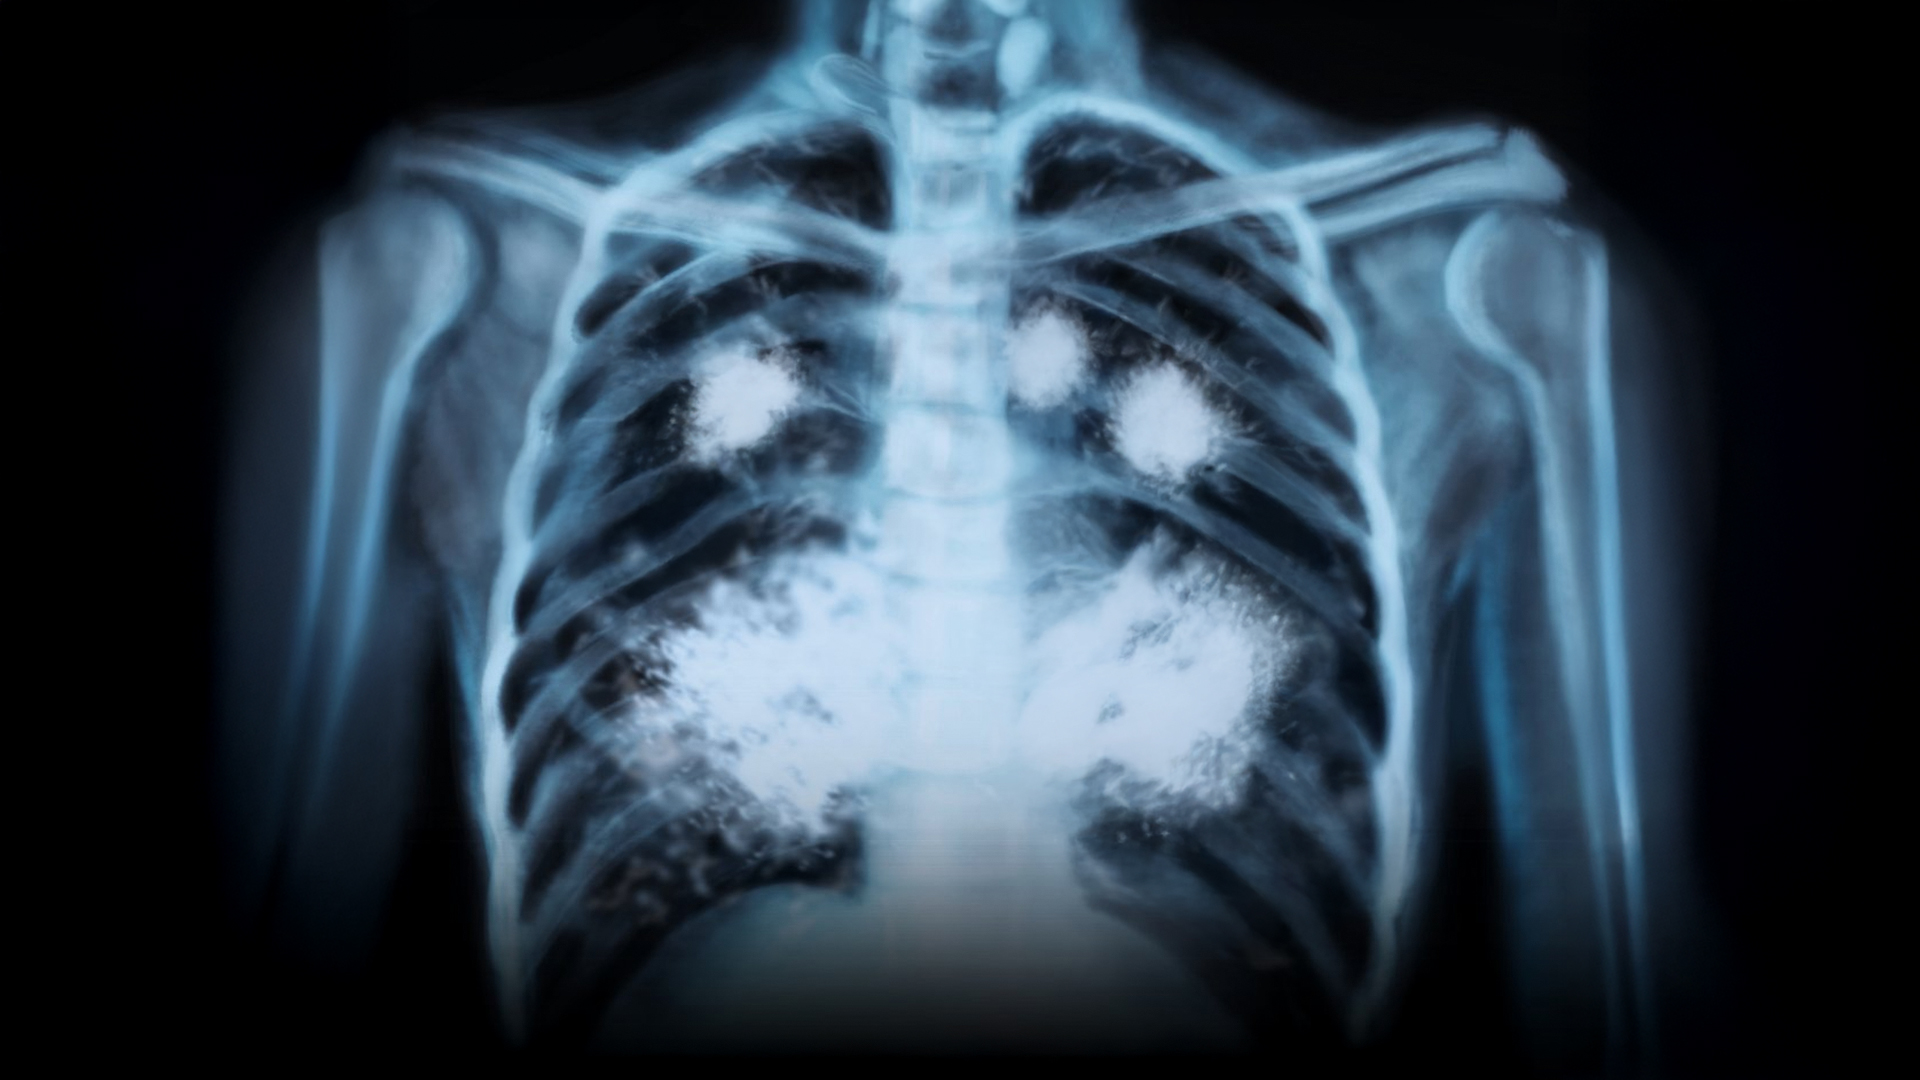

Esto le está haciendo el vapeo a tus pulmones

👉 El vapeo puede causar una enfermedad pulmonar rara, irreversible y mortal.

Se llama bronquiolitis obliterante, y destruye poco a poco los bronquiolos de los pulmones.

Provoca tos, falta de aire, dolor al respirar y, con el tiempo, deja los pulmones completamente dañados.

No tiene cura.